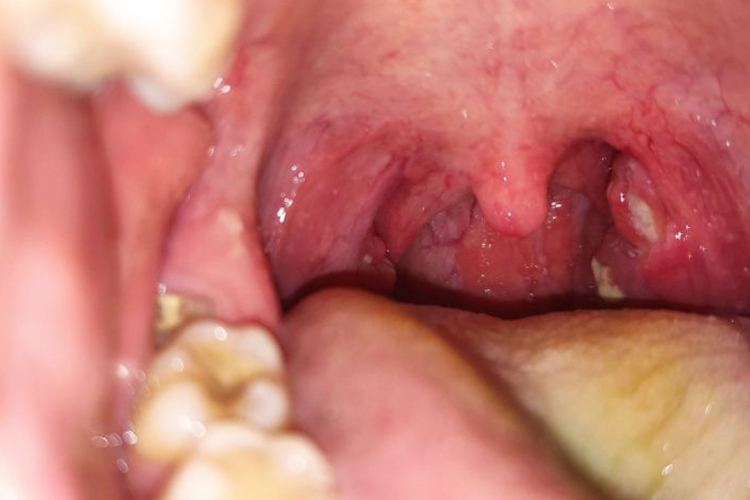

扁桃体化脓多指急性化脓性扁桃体炎,表现为腭扁桃体肿大,表面有黄白色脓点,经过治疗后,脓点逐渐消失,局部肿胀消退。

扁桃体化脓多指急性化脓性扁桃体炎,体格检查患者呈急性热病容,扁桃体肿大明显,表面有黄白色脓点,或在隐窝口有渗出物,咽部黏膜呈弥漫性充血。

经过治疗后,扁桃体肿大逐渐消退,其表面的黄白色脓点消失,咽部黏膜无充血,隐窝口无渗出物,同时患者的其他伴随症状也逐渐缓解并消失。